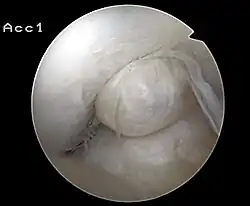

Die höchste diagnostische Sicherheit bietet die diagnostische Arthroskopie (Gelenkspiegelung). Dieses Verfahren stellt für die Diagnosestellung des Kreuzbandrisses den Goldstandard dar. Das Verfahren ist zwar minimalinvasiv, stellt aber in jedem Fall einen mit gewissen Risiken behafteten chirurgischen Eingriff in das Knie des Patienten dar.[94] Da jedoch die operative Behandlung eines Kreuzbandrisses in der Regel arthroskopisch (therapeutische Arthroskopie) durchgeführt wird, ergibt sich die Möglichkeit die Therapie, beispielsweise in Form einer Kreuzbandteilresektion (bei Anriss) oder einer Refixation des ausgerissenen Bandes, unmittelbar nach der diagnostischen Arthroskopie durchzuführen. Mit der zunehmenden Verbreitung von Kernspintomographen hat die Anzahl der rein diagnostischen Arthroskopien in den letzten Jahren deutlich abgenommen.[95][96] Die diagnostische Arthroskopie ist aber nach wie vor zur sicheren Abklärung der Diagnose einer Kreuzbandruptur – bei unklarer klinischer Befundung und unklarer MRT – das Mittel der Wahl.[94]

Arthroskopie

Der eigentliche Eingriff beginnt mit der Einführung des Arthroskops in das Knie des Patienten. Die Diagnose »Kreuzbandriss« kann so nochmals bestätigt werden. Andere Verletzungen, insbesondere des Meniskus, können vor der Rekonstruktion des Kreuzbandes versorgt werden.